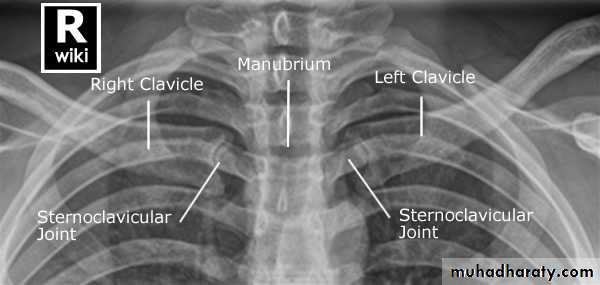

4-Sternoclavicular joint:

Adult Sternoclavicular Joints - PA Oblique